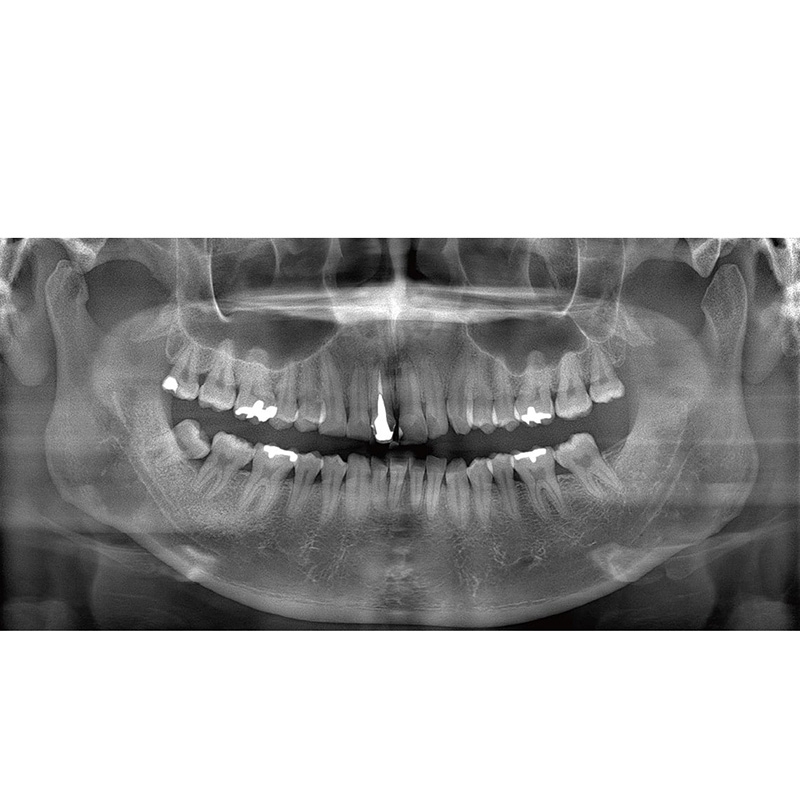

Information / DemoPanorama 2D

Veraview (IC5 HD) Spezifikationen

High-Speed-Modus - 5,5 Sek./192 µm

High-Definition Modus - 10 Sek./96 µm - Lichtvisiere: